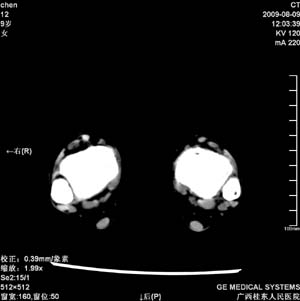

标题: PED2867:右侧内踝肿胀,骨质改变,请各位老师会诊 [打印本页]

标题: PED2867:右侧内踝肿胀,骨质改变,请各位老师会诊

九岁小朋友,近期左侧内踝疼痛,局部肿胀,平时无特殊,近期经常溜干冰

对不起,是右侧内踝肿胀

双踝关节骨质及发育未见异常。

左侧内踝密度增高,请结合临床!